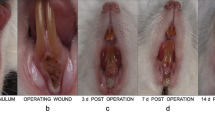

The laser-treated surgical regions were circular lesions with lost surface mucosa. The remaining mucosa immediately around the laser-induced wounds appeared as pale whitish foci. There was minor bleeding from the wounds, which was stopped by gauze compression within a very short time (Fig. 1A).

The gross appearance of the rabbit’s maxilla after laser perforation. A Immediately after surgery. Hemostasis was achieved completely. B Three days after surgery. The wound formed an ulcer-like defect in the mucosa (arrow). Localized slightly erythematous tissue was noted around the defect. C Seven days after surgery. The mucosa at the surgical area had healed completely. There were no signs of swelling or erythematous tissue

All of the rabbits tolerated laser surgery without postoperative difficulties. The wound formed an ulcer-like defect in the mucosa at the treated area. There was no sign of swelling or exudate. Localized slightly erythematous tissue was noted around the defect (Fig. 1B).

After seven days the mucosa in the surgical area had healed completely. There were no signs of swelling or erythematous tissue (Fig. 1C). Histological examination showed that epithelial generation was evident, with varying degrees of hyperparakeratosis. Fibroblasts and mononuclear inflammatory cells were noted in the submucosa, and the infiltration of neutrophil leukocytes had decreased (Fig. 4A). Different healing processes could be observed in the maxillary and mandibular bone: in the maxilla, carbonized char was partially absorbed and the gap between char and bone tissue had diminished; the granulated tissue was characterized by intensive fibroblasts (Fig. 4B); in the mandible, only minimal changes in the carbonized char were observed; the granulated tissue was still characterized with an infiltration of inflammation leukocytes and fibrin, and organization was evident.